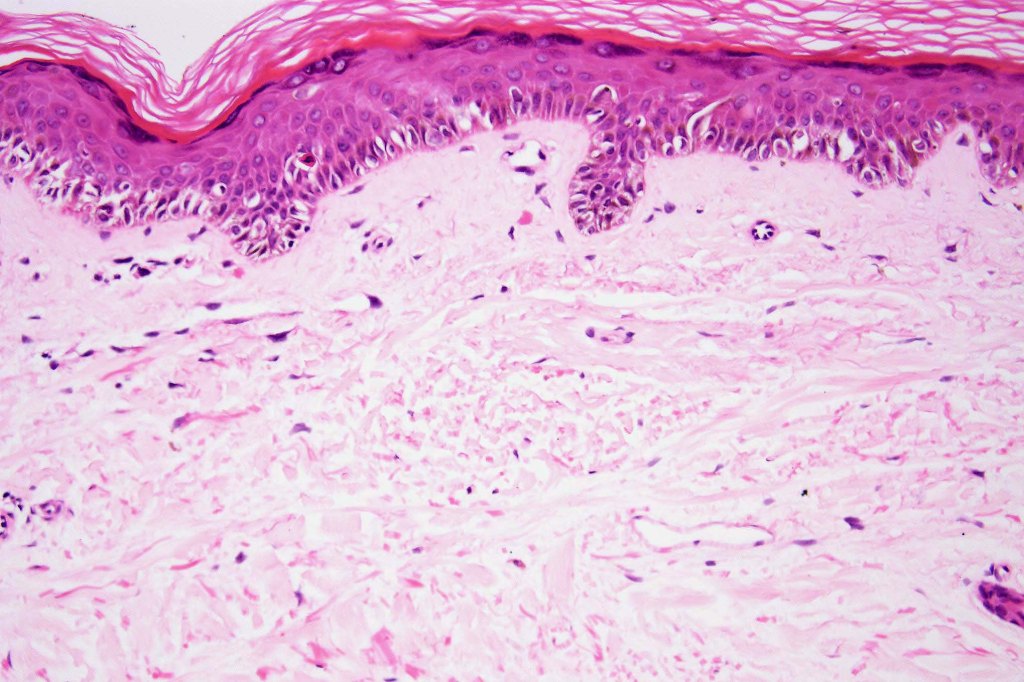

Histological features

- A broad lentiginous proliferation of atypical melanocytes unasscoiated with any loss of the rete ridges

7. Fibroplasia not seen and elastosis is either mild or absent